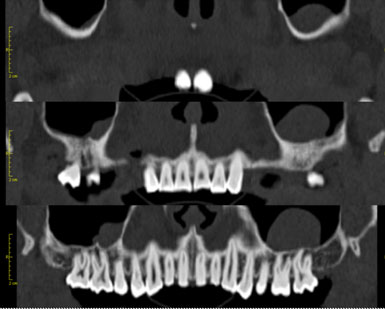

Este estudio dental genera reconstrucciones en múltiples planos de mandíbula, maxilar superior y piezas dentarias. Ofrece grandes ventajas con respecto a los estudios radiográficos dentales convencionales como la radiografía intraoral, la ortopantomografía y la cefalometría lateral.

El motivo más común para solicitar un tac dental es la evaluación prequirúrgica del implante dental. Aunque también puede prescribirse en el seguimiento de la evolución del implante y en el diagnóstico de enfermedades de mandíbula y maxilar superior.

En el campo de la implantología, si la ortopantomografía obtenida previamente no es concluyente para valorar la viabilidad y las características del implante, el tac dental ofrece al odontólogo la mayor precisión de anatomía dentaria y de calidad del hueso subyacente, permitiendo así decidir la viabilidad, las dimensiones y la posición final del implante. Entre otros parámetros, el TC dental permite valorar aspectos fundamentales para el odontólogo en el estudio anterior al implante, como son: